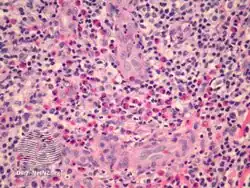

| Epithelioid haemangioma in skin | |

Epithelioid haemangioma is a non-cancerous tumor typically found in skin and soft tissue of usually the head and neck region, where it presents with reddish-pink itchy painful bumps.[1] It can occur in bone as a type of vascular tumor of bone, where it can give rise to pain and swelling.[2]

It is made up of well-formed blood vessels lined by lymphocytes and eosinophils (types of white blood cells).[1]